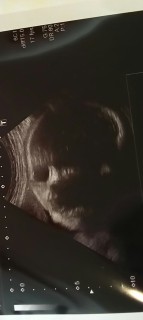

写真:35w0d:ちいちえさん:2658g

毎回4Dしてくれるけど

35週にして初めてお顔が見えた!^ ^

お口をもにゅもにゅしてて

全体的にぷっくり^ - ^

一気に早く会いたくなりました!!

2700超えの大きめボーイです(^^)

寝顔は、お父さんに似てるかな?お母さんに似ないでほしい(笑)順調みたいでーす!一週間後また、会えるねー♪